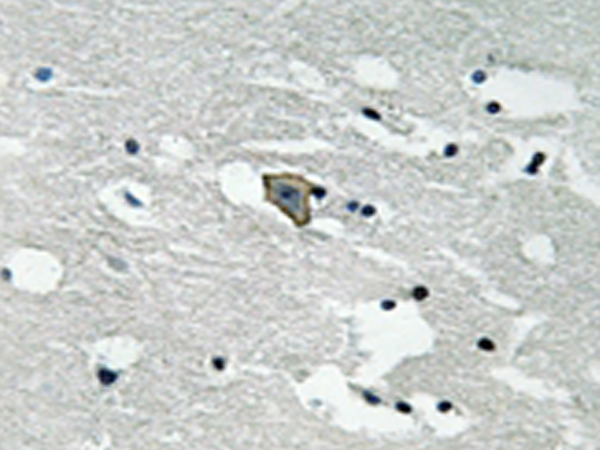

IHC positive control: |

Human brain tissue |

IHC Recommend dilution: |

50-100 |